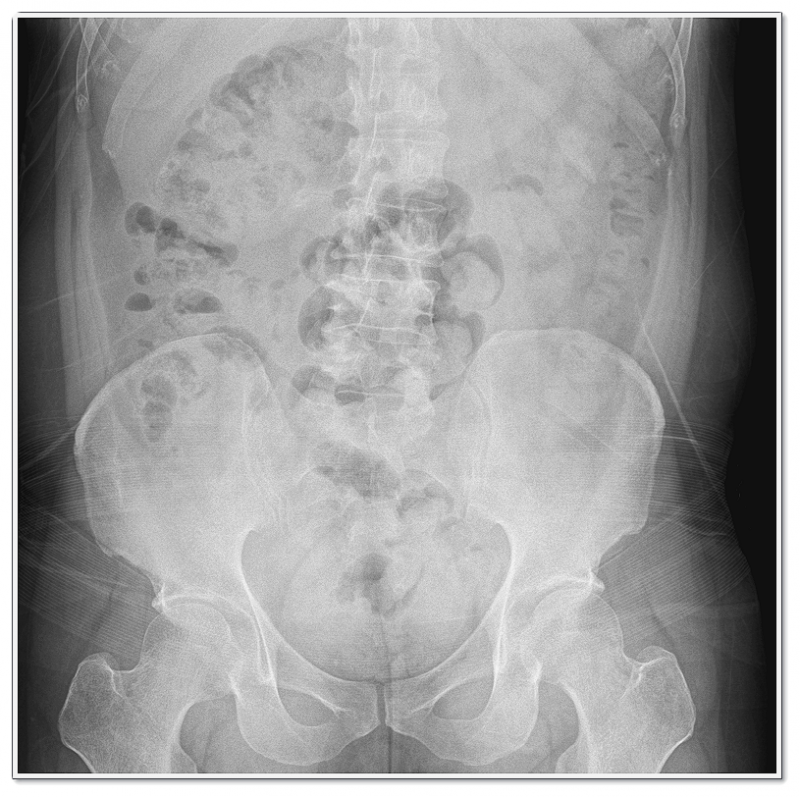

수술 전 꼭 알아야 할 허리디스크 비수술 치료법

허리디스크는 단순히 ‘디스크가 튀어나온 질환’으로만 볼 수 없습니다.

척추뼈 사이에 위치한 추간판(디스크)은 충격을 흡수하고 척추의 유연성을 유지하는 역할을 하죠.

문제는 디스크가 돌출되면 그 주변 신경을 자극하면서 통증과 방사통이 생긴다는 점이에요.